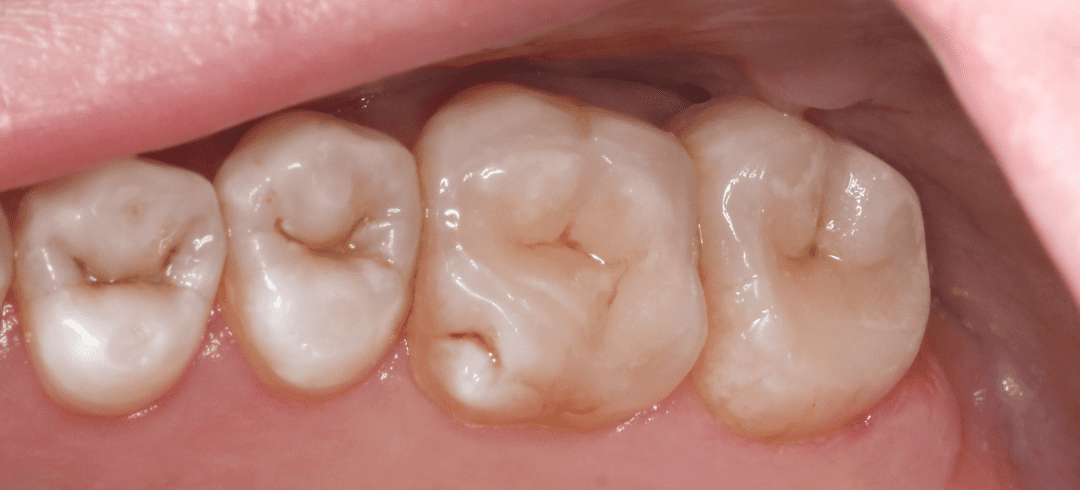

Восстановление эстетики с помощью виниров и вкладок (часть 2)

Восстановление эстетики с помощью виниров и вкладок (часть 1)